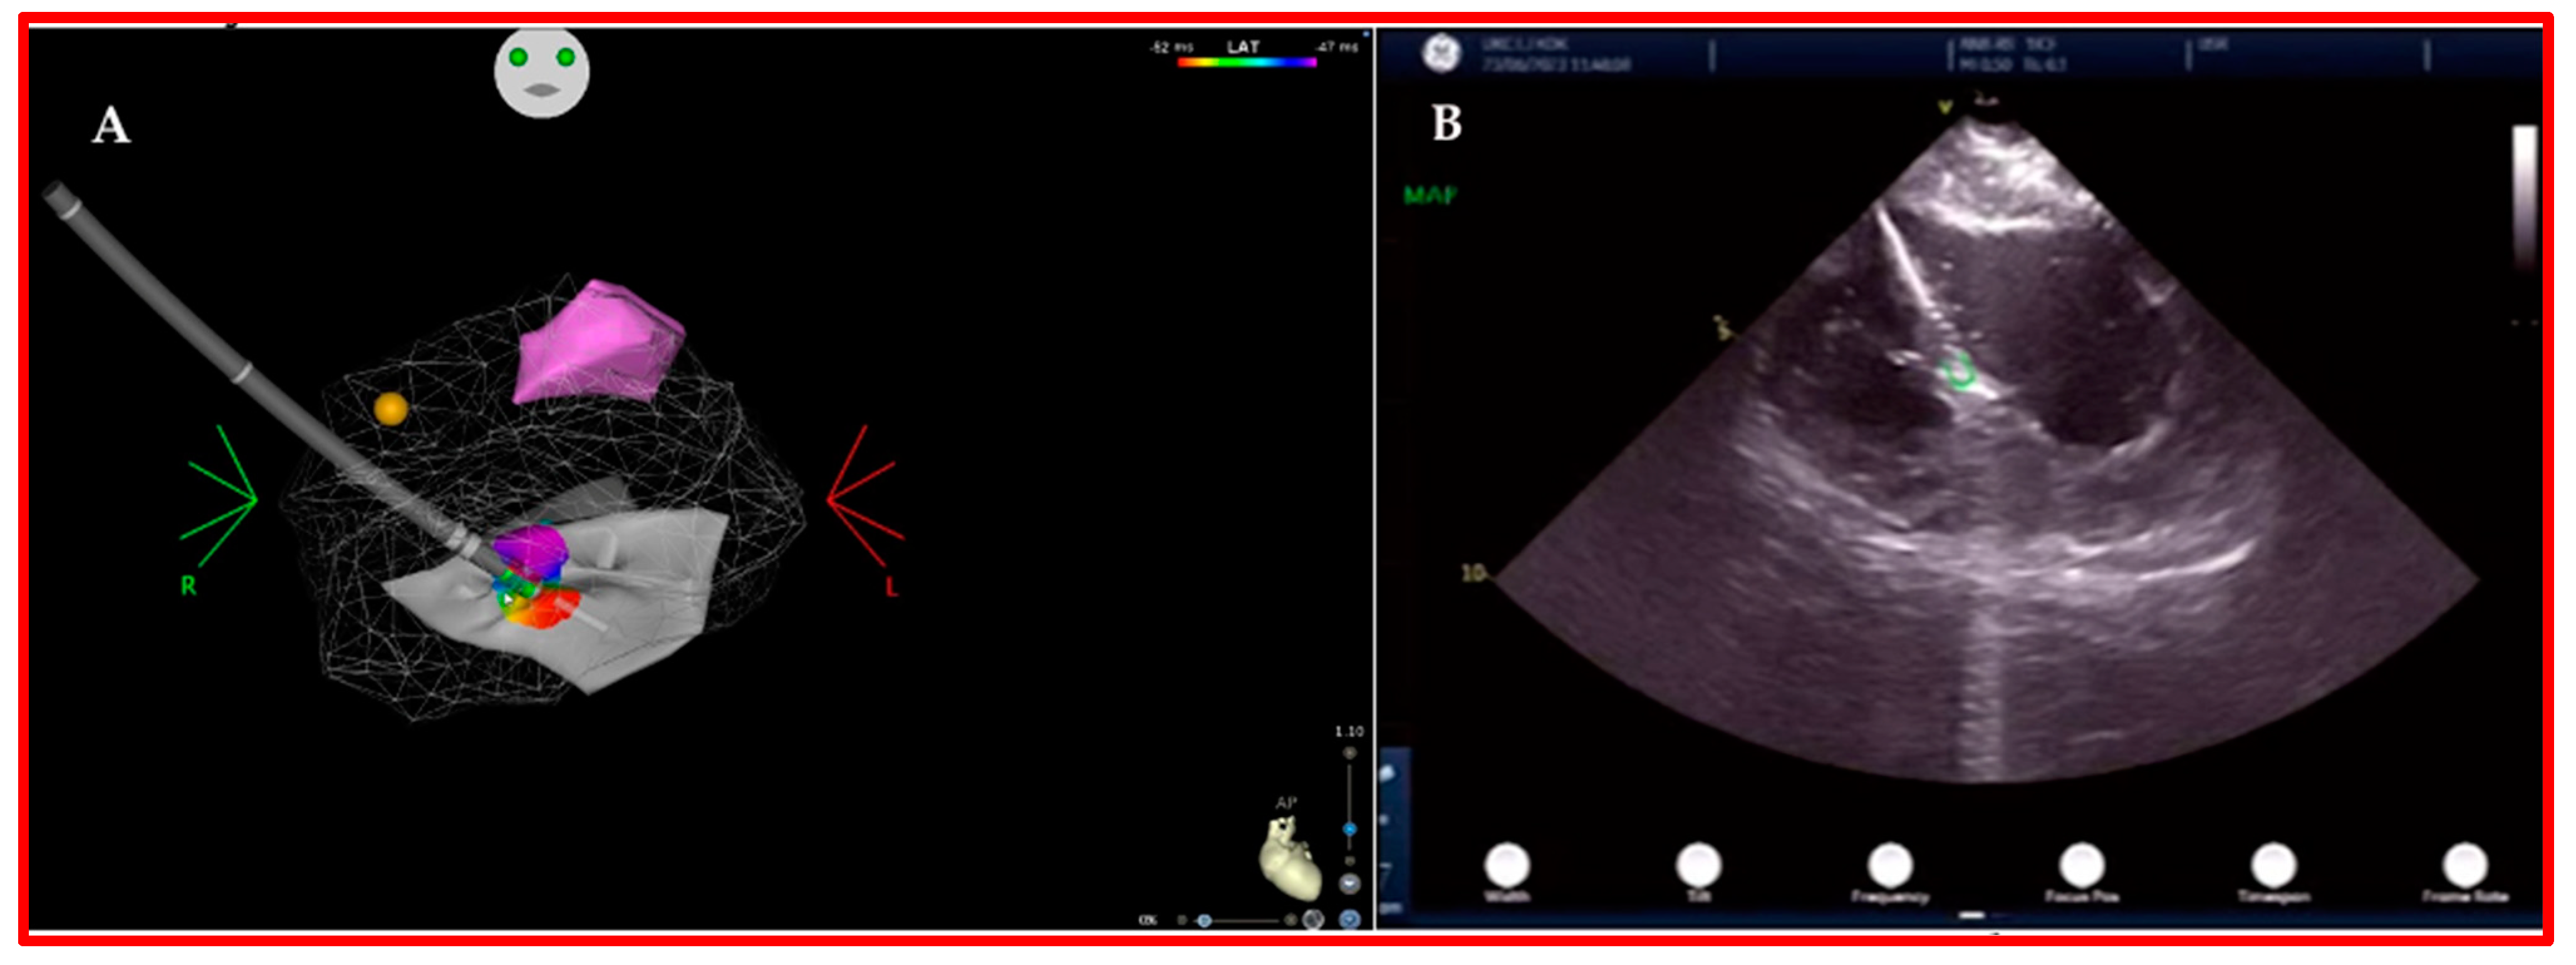

3.1. Intracardiac Echography

3.2. Three-Dimensional (3D)-Mapping Systems

4. Our Experience and Workflow